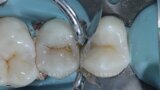

Management of proximal posterior lesions- A case report